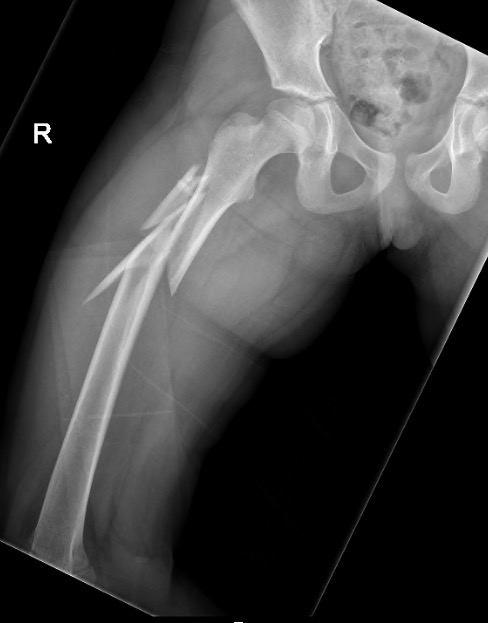

Вот, что получилось.

Александр, Почему в шейку и головку? почему не в направлении малого вертела привели блокирующий винт? Это оригинальный винт или...?

почему бы и не в шейку... Если есть такая дырочка и в гвозде, и в направителе. В physis винт не проникает.

Винт, конечно, из набора.

Винт, который проходит перпендикулярно зоне роста проблем не вызывает. Таким образом делается эпифизиодез при юношеских эпифизиолизах и в перспективе на рост кости не влияет. Поэтому производитель не зря придумал шеечный винт в данном стержне

Эпифизиодеза у нас в планах не было, поэтому винтик не до суставной поверхности. В общем, если железка не проходит через зону роста, то и беспокоиться особо не о чем, правильно?

На прямой проэкции видно, что винт проходит физиодезный мостик. Даже если был бы длиннее, тоже не критично.

Супер, гвоздь с латеральный точкой доступа! Кто производитель?

В чем смысл настолько латерального захода, почему так спереди гвоздь и настолько кзади винт?

смысл латерального захода - отдалиться от сосудов, питающих у детей головку бедра. Если сделать снимок с чуть большей внутренней ротацией, не будет складываться впечатления, что он спереди. Винтик... Он внутри шейки, не торчит. Этого, полагаю, достаточно. Был бы он кпереди на несколько мм, это бы ничего не прибавило